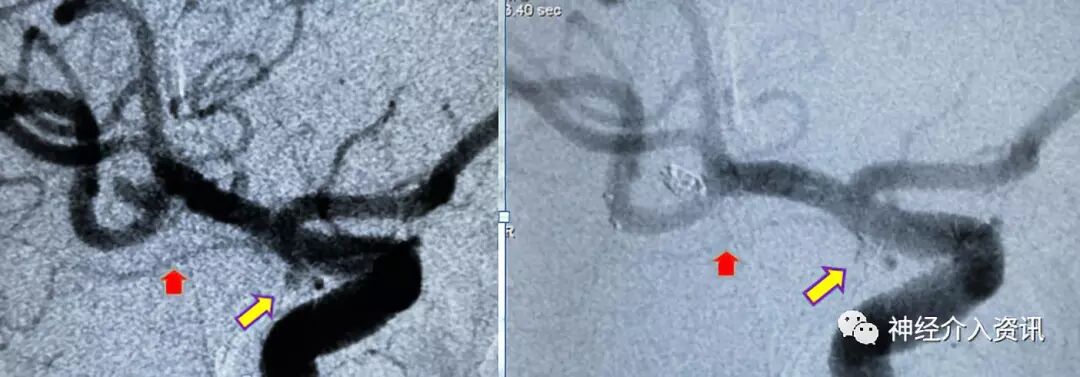

图二 多发动脉瘤

图三 大脑中动脉瘤致密栓塞

图四 黄箭头显示应用一枚Axium™ Prime ES 1mm*3cm弹簧圈将脉络膜前动脉动脉瘤致密栓塞,脉络膜前动脉保存良好(红箭头)

患者以“劳累后突发昏迷12小时”为主诉入院,入院查体颈强直,脑膜刺激征阳性,余神经系统查体无异常。头部CTA提示蛛网膜下腔出血,右侧大脑中动脉动脉瘤。完善术前准备后,于次日行全脑血管造影术,造影见右侧大脑中动脉动脉瘤,M1M2分叉处动脉瘤,2.8*2.5mm,瘤颈3.0mm;另一处脉络膜前动脉动脉瘤,1.5*1.0mm,瘤颈1.5mm。计划同时处理两处动脉瘤。

先处理大脑中动脉分叉部动脉瘤,应用Echelon-10微导管在微导丝导引下置于动脉瘤的中心,将支架导管置入同侧大脑中动脉M2中,释放4*15mm Solitaire™ AB支架一枚,跨越动脉瘤颈,应用Axium™ Prime ES 1.5mm*3cm弹簧圈及1mm*3cm弹簧圈将大脑中动脉动脉瘤致密填塞,在栓塞过程中微导管始终保持稳定,弹簧圈顺利推送无顶管现象,完成对该动脉瘤的栓塞;继续处理右脉络膜前动脉动脉瘤, Echelon 10在微导丝导引下置于动脉瘤的中心,释放3.5*15mm支架一枚,跨越动脉瘤颈,应用一枚Axium™ Prime ES 1mm*3cm弹簧圈将动脉瘤致密填塞,完成对两个动脉瘤的栓塞。